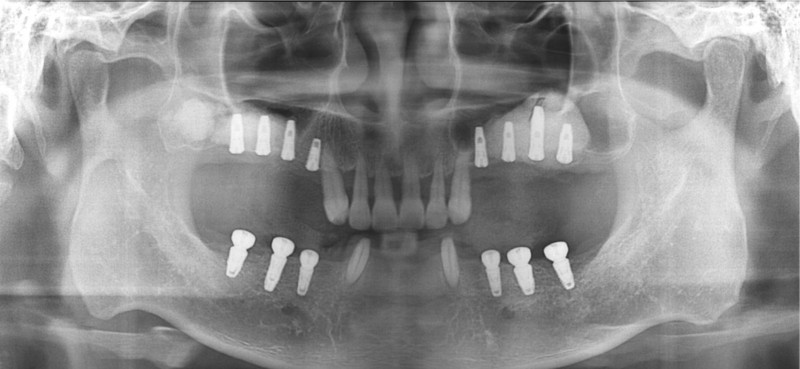

중간과정 ▼

상악동거상술 Sinus